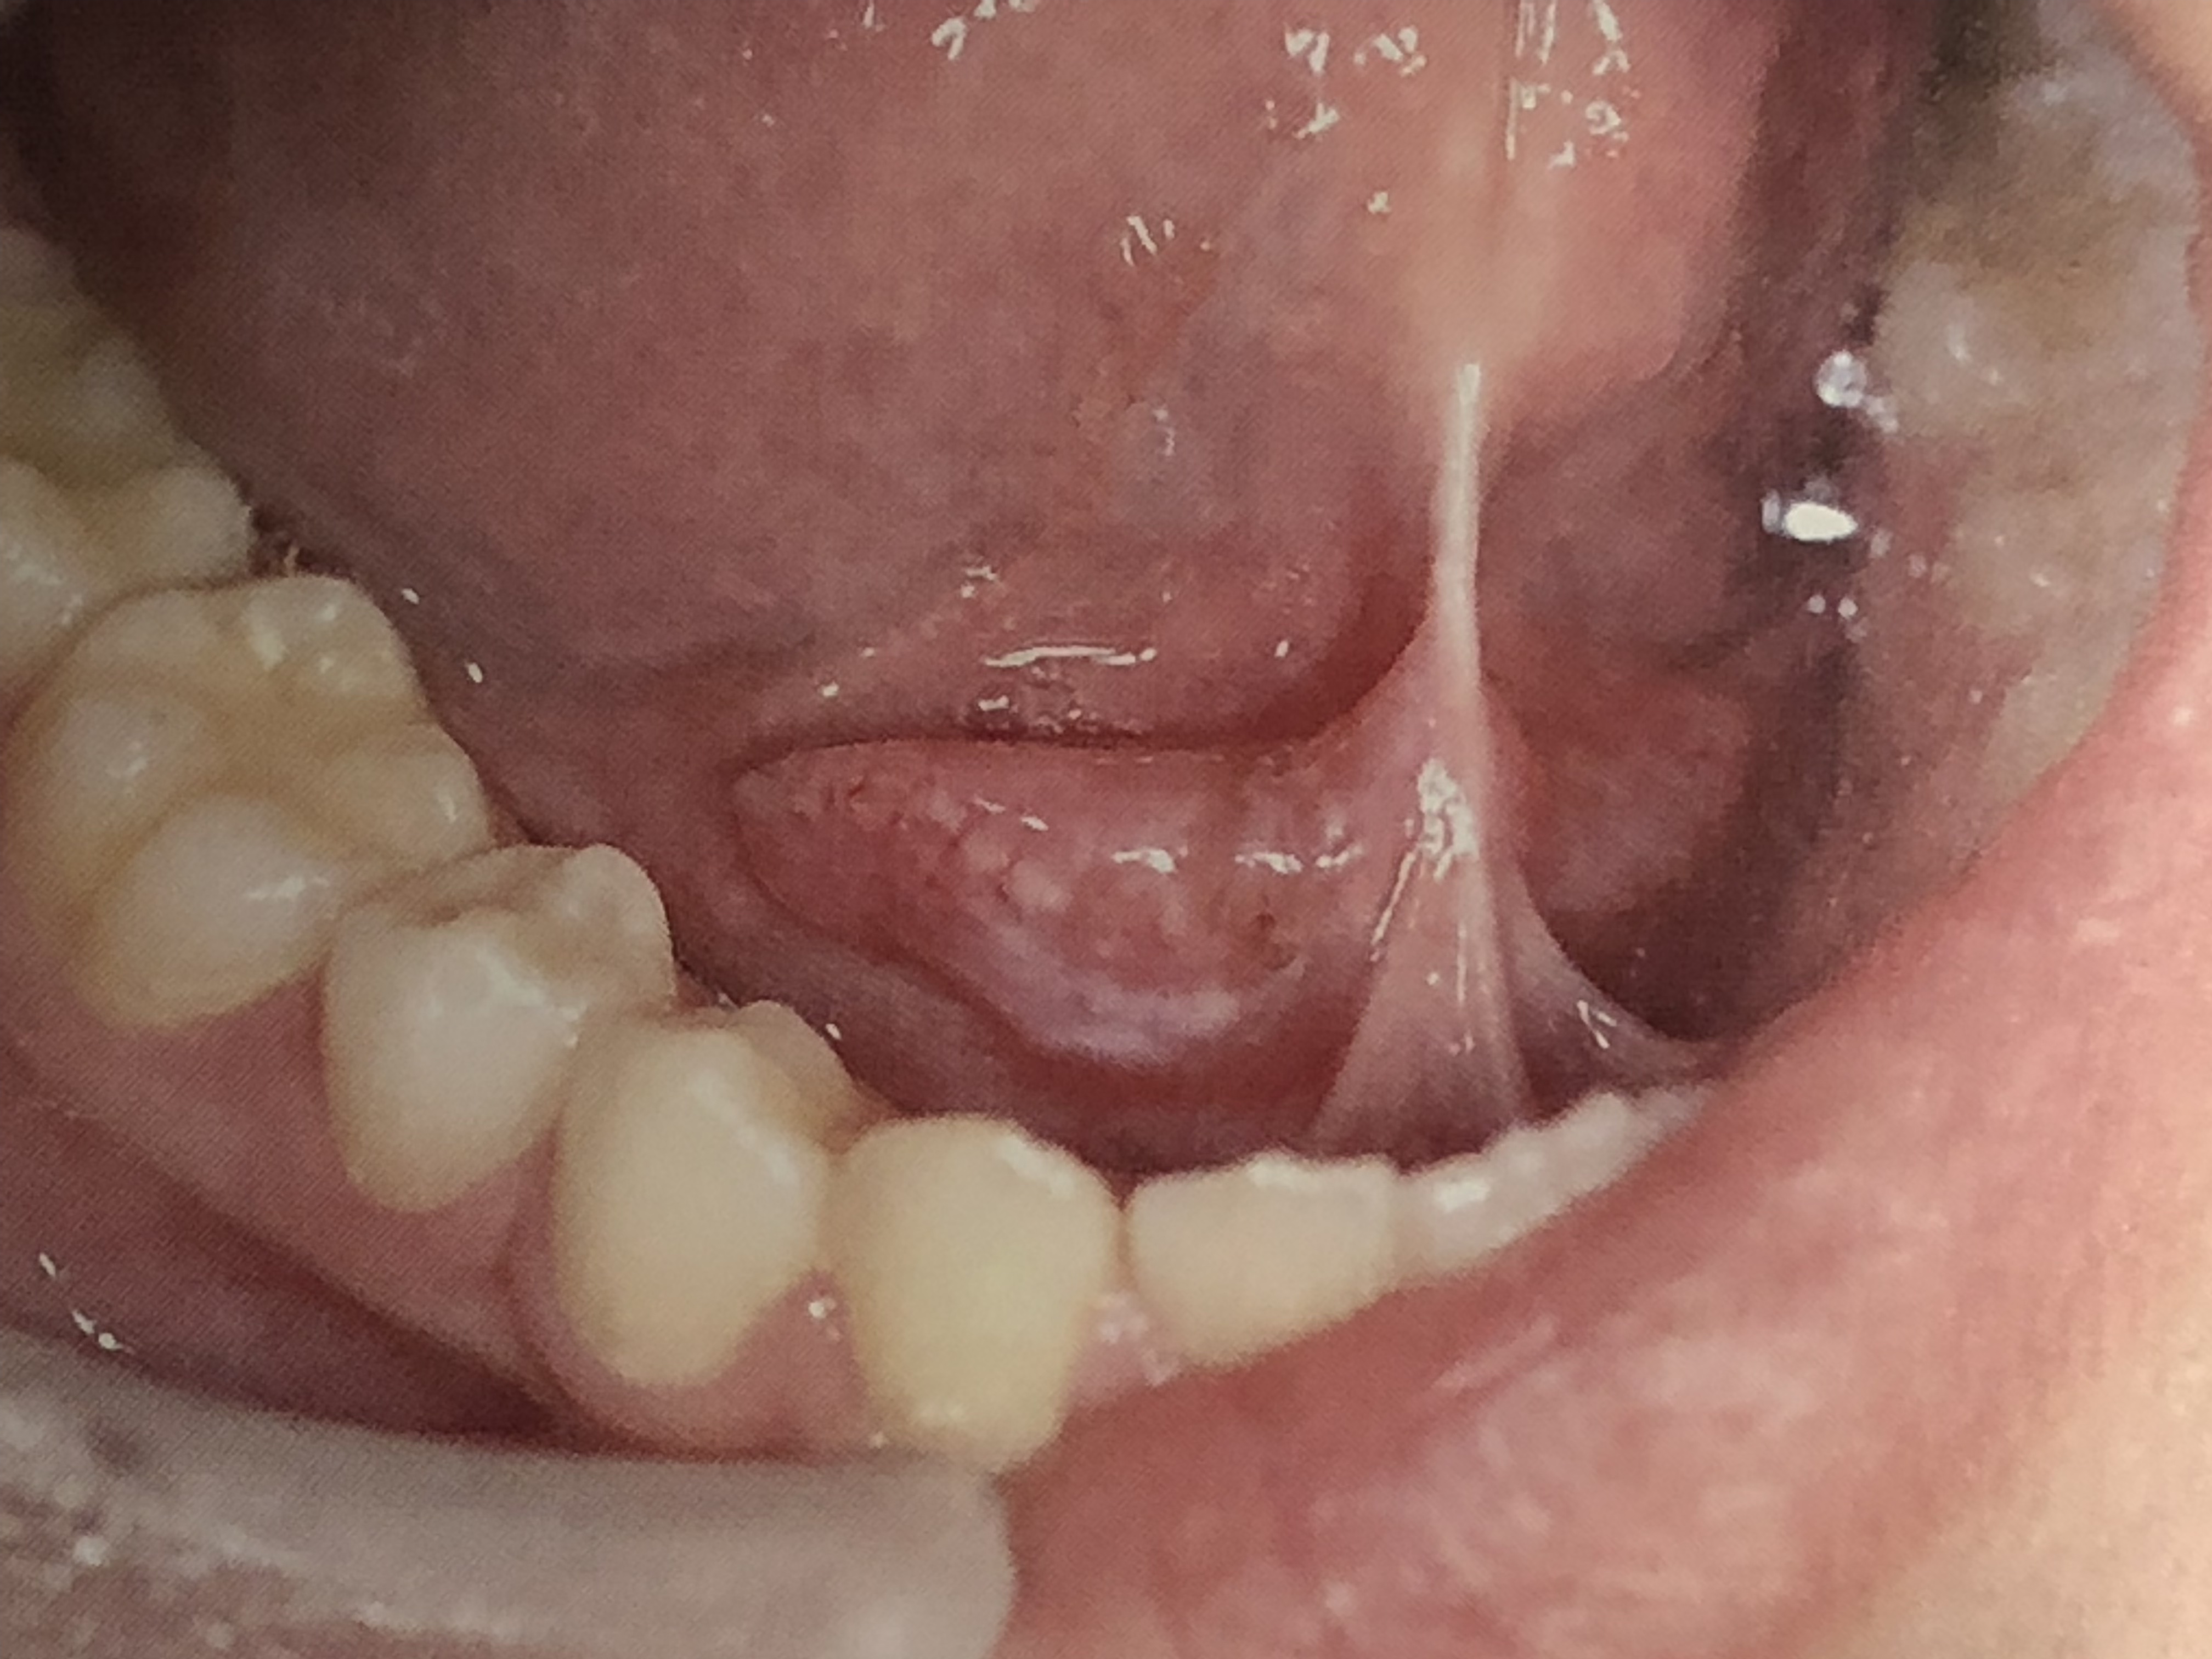

口腔粘膜に現れる病変の色は、赤、白、黒、黄の4色です。

その中で初期のガンを見分けるためには、赤、白、黒に注意します。

口腔ガンを疑う臨床的変化は?

初期ガンは

口内炎が2週間以上治らない。

経過観察中の白斑の色や形が変化してきている。

口内炎の部分から出血がある。